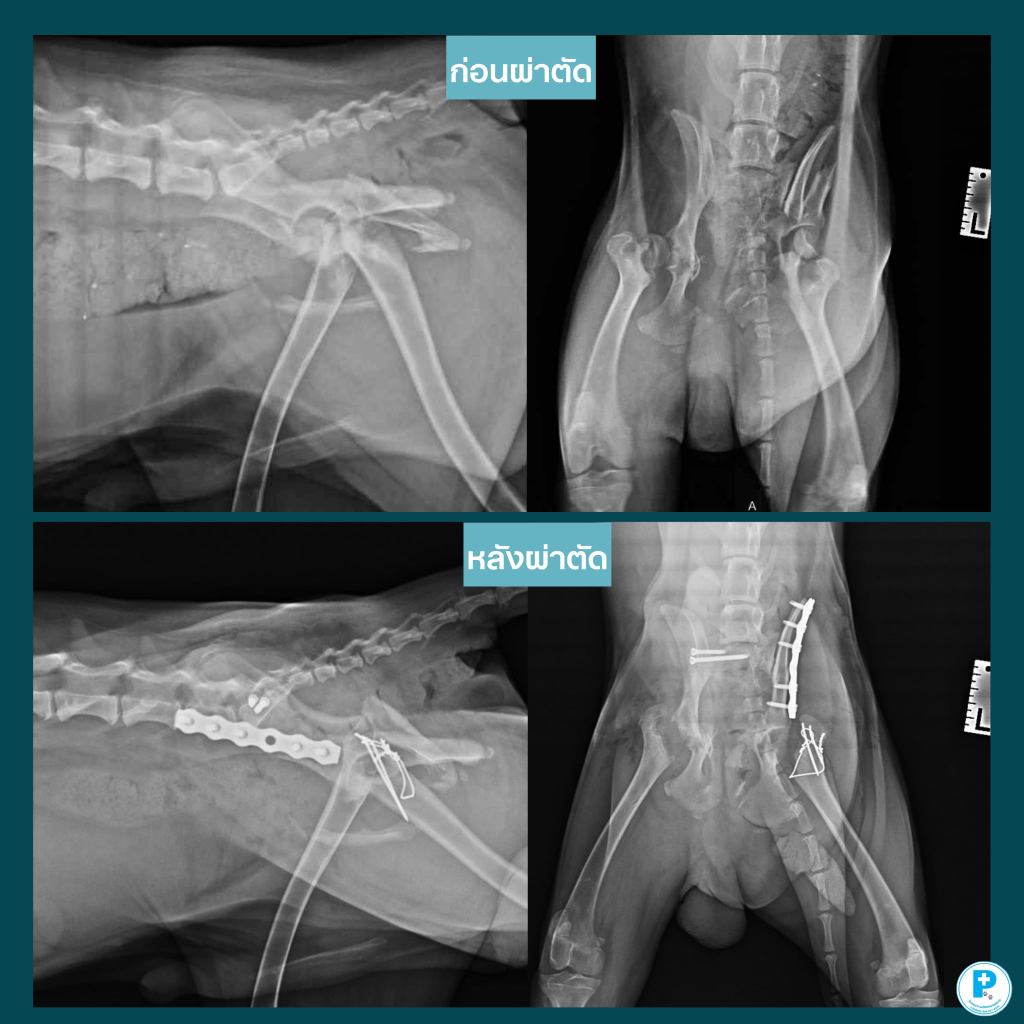

- เคสนี้ทั้งหนักทั้งลุ้น…แต่น้องสวยสู้มาก

“น้องสวย” แมวอายุ 12 ปี ประสบอุบัติเหตุโดนรถทับบริเวณเชิงกราน ทำให้เกิดการบาดเจ็บหลายตำแหน่ง ทั้งข้อเชิงกรานหลุดและกระดูกแตก

ก่อนผ่าตัด ทีมสัตวแพทย์ได้ทำการตรวจหัวใจ (Echo) และปรับสภาพร่างกายอย่างละเอียด รวมถึง ตรวจเลือดชุดมาตรฐาน เพื่อประเมินความพร้อมในการวางยาสลบ โชคดีที่ไม่พบโรคหัวใจ

มีการสวนท่อปัสสาวะเพื่อตรวจระบบทางเดินปัสสาวะ และไม่พบการแตกของกระเพาะปัสสาวะ

จากภาพเอกซเรย์ อาจดูเหมือนว่า SI ไม่ได้หลุด แต่ในการตรวจจริง คุณหมอได้ทำการคลำและโยกเชิงกราน พบความไม่ประสานกันของข้อต่อ (instability)

ดังนั้น การวินิจฉัย SI luxation ในเคสนี้ อาศัยการตรวจแบบ manual examination ร่วมด้วย ไม่ใช่ดูจากภาพเอกซเรย์เพียงอย่างเดียว

สิ่งสำคัญคือ การวางแผนผ่าตัดกระดูกจำเป็นต้องอาศัยการประเมินโดยสัตวแพทย์ศัลยกรรมกระดูกอย่างละเอียด ไม่ใช่แค่การอ่านภาพเอกซเรย์ แต่ต้องรวมถึงการตรวจร่างกายจริงของสัตว์ป่วยด้วย

การผ่าตัดที่ทำ:• Right SI lag screw fixation

• Left ilial plate fixation

• Left FHNE (Femoral Head and Neck Excision)

• Dental scaling

หลังผ่าตัด น้องสวยฟื้นตัวได้ดี ปลอดภัย และขณะนี้แอดมิทเพื่อเฝ้าดูอาการอย่างใกล้ชิด

เคสนี้ย้ำให้เห็นว่า “การเตรียมตัวก่อนผ่าตัด” โดยเฉพาะในสัตว์สูงวัย สำคัญมากจริงๆ และการวินิจฉัยที่แม่นยำต้องอาศัยทั้งภาพถ่ายรังสีและประสบการณ์ของสัตวแพทย์ร่วมกันผ่าตัด: สพ.ญ.ณัฐฐ์ธวรรณ โสภิพันธ์ (หมอพลอย)